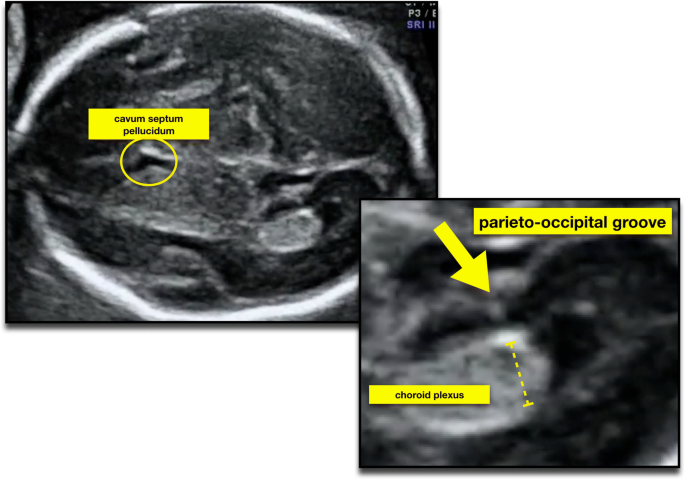

Ultrasound Atlas Glowm